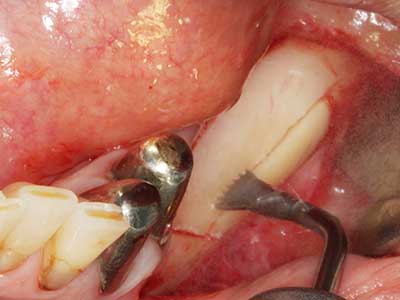

En la extracción de bloques óseos la piezocirugía también presenta ventajas adicionales: Además de la alta precisión en la osteotomía que ya se ha descrito antes, se ha comprobado que el uso de los delgados insertos de sierra resulta especialmente cuidadosas con el hueso. Frente a esto, sobre todo cuando se usan las fresas de Lindemann, cabe esperar pérdidas en la extracción significativamente más altas debido al mayor grosor de la parte frontal del cabezal (Lakshmiganthan, Gokulanathan et al. 2012). La separación basal que se necesita en particular en los injertos de bloque extraídos de forma retromolar se ve facilitada mediante sierras perpendiculares especialmente previstas a tal fin, lo que permite considerar que la cirugía piezoeléctrica es un procedimiento preciso y seguro para la obtención de bloques de hueso en el área retromolar (Happe 2007) (fig. 1-12).

Si es preciso realizar intervenciones quirúrgicas en las que el hueso está en contacto directo con estructuras sensibles, como son los vasos sanguíneos o los nervios, los instrumentos rotativos presentan un enorme potencial de provocar lesiones iatrogénicas. Así, precisamente en la representación de nervios después de una lesión iatrogénica, o en el transcurso de la lateralización de un nervio para resecciones, reconstrucciones o incorporación de implantes, los equipos piezoeléctricos pueden resultar muy útiles para preparar la tapa ósea y retirar las partes de tejido duro cercanas al nervio (fig. 17-20). Por lo general, un ligero contacto del cordón nervioso con el inserto piezoeléctrico no tiene consecuencia alguna; ahora bien, un procedimiento poco cuidadoso con movimientos tipo sierra o piezas de trabajo sobre la base ósea aún existente puede provocar lesiones nerviosas temporales o incluso permanentes. Con todo, el riesgo de sufrir una lesión de este tipo se considera significativamente inferior que en los casos en los que se utilizan sierras y fresas (Pereira, Gealh et al. 2014).